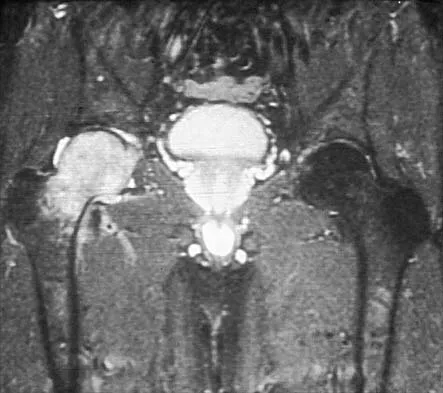

Question 27

A 3-year-old child has refused to walk for the past 2 days. Examination in the emergency department reveals a temperature of 102.2 degrees F (39 degrees C) and limited range of motion of the left hip. An AP pelvic radiograph is normal. Laboratory studies show a WBC count of 9,000/mm3, an erythrocyte sedimentation rate (ESR) of 65 mm/h, and a C-reactive protein level of 10.5 mg/L (normal < 0.4). What is the next most appropriate step in management?

Explanation

A 10-year-old girl with a monoarticular pattern of juvenile rheumatoid arthritis (JRA) has had a 3-cm limb-length discrepancy since age 8 years when inflammation in the right knee came under good medical control. Because her right leg is longer, the patient states that she would like her legs to be close to equal in length in the future. A growth-remaining chart is shown in Figure 14. Management should consist of

Explanation